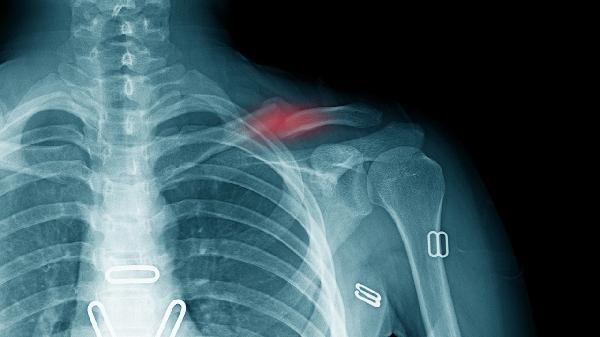

锁骨折拆钢板休息多久?

1、一般情况下,拆钢板后休息多久取决于患者的具体情况,约3-6个月。

2、锁骨骨折是常见的创伤性骨折之一,需要通过手术拆除钢板进行治疗。如果是从术后康复期结束到恢复期开始,需要在这个阶段进行康复训练,帮助肩膀和手臂的肌肉恢复正常功能。康复阶段的持续时间取决于个人情况和治疗方案,通常需要6-8周。

3、如果中老年患者或儿童骨折,恢复期会因体质虚弱和骨骼肌发育不良而延长。在这种情况下,术后需要休息1-2个月。部分患者肩周炎、关节炎等并发症是由于肩膀和手臂肌肉的过度使用引起的。在这种情况下,他们应该在手术后休息3-6个月。

4、锁骨骨折钢板手术后的康复需要在医生的指导下进行,并注意休息和恢复的时间。如果术后出现疼痛、发热、手臂活动有限等症状,应及时就医,并在医生的指导下进行相应的治疗。